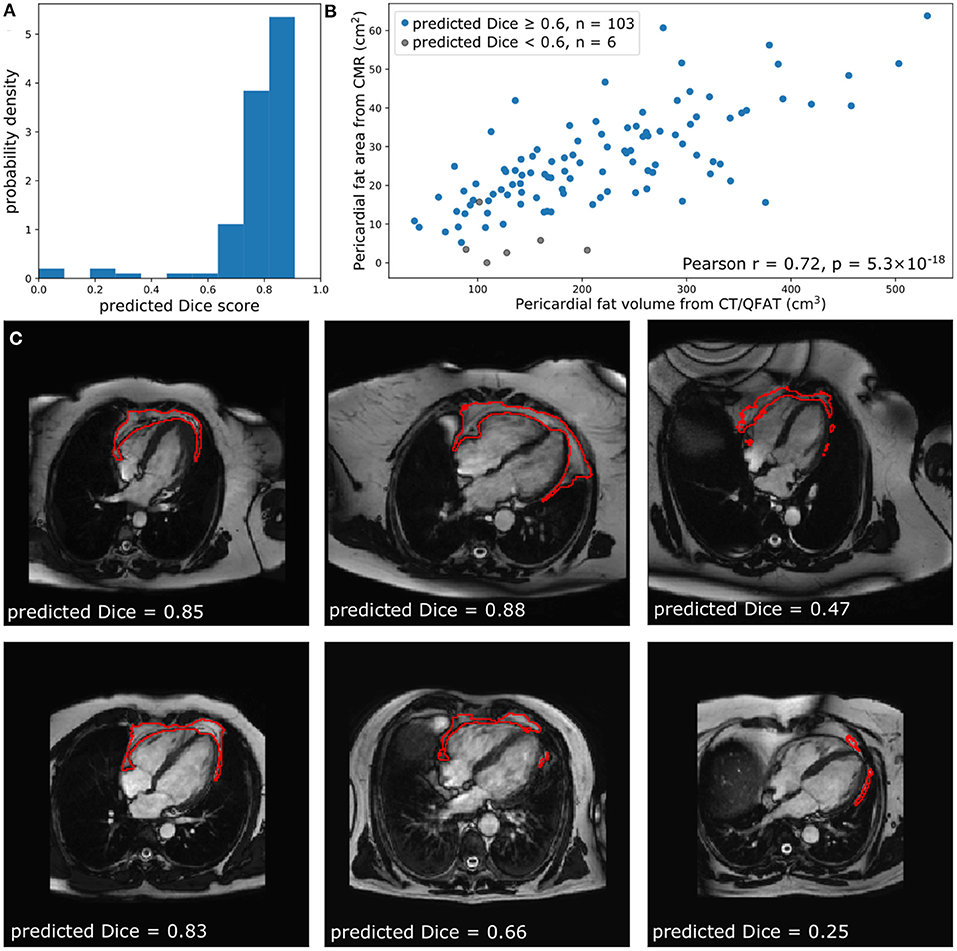

The performance of the automated segmentation within the test set relative to manual segmentations was good and very similar to the agreement between human observers (mean Dice score = 0.8). This was the case both for raw segmentation metrics (Table 1) and under Bland–Altman analysis (Figures 3E–H). Arguably, this is the best performance that may be achieved by an automated segmentation algorithm and reflects the inherently challenging nature of the PAT segmentation task. A few cases (n = 4, 4.5%) had poor segmentation quality (Dice score <0.6) (Figures 3A–D) and very large Hausdorff distances. This underlines the importance of the in-built QC feature, which would flag such cases. We also successfully applied the automated segmentation to the whole UKB imaging cohort (n = 45,519); 94.3% of cases (n = 42,928) had predicted Dice score of medium or good quality (mean predicted Dice score = 0.77). Example segmentation results from the UKB test dataset can be seen in Figure 3I. The automated segmentation also performed well in the external EVINCII dataset, with the majority of studies having medium/good segmentation quality (n = 103, 94.4%), with an overall mean predicted Dice score of 0.78 (Figure 4A). Running on a laptop PC with an Intel® Core™ i7-1165G7 processor, using a MC sample size (N) of 15, the model and QC step took 2.1 s, including image pre-processing and final estimation of Dice score.

Figure 4. Comparison of quantified PAT from CT and CMR. (A) The predicted Dice scores of the segmented data. (B) Correlation between PAT volume quantified via QFAT software and PAT area quantified using our method. Subjects with a predicted Dice < 0.6 were excluded from Pearson analysis. (C) Some example CMR images, their automatically segmented PAT, and the predicted segmentation quality are also shown for reference.

Correlation of Automated CMR PAT With CCT PAT Quantification

Within the EVINCII dataset, we tested the correlation of CMR PAT measures derived using our automated analysis with PAT derived using the QFAT tool from paired CCT scans. CMR studies with poor segmentation quality (predicted Dice score <0.6) were excluded from the analysis (n = 6). For illustration, we present example segmentations with a range of Dice scores in Figure 4C. There was a strong, statistically significant correlation between CCT PAT volume and CMR PAT area (Pearson r = 0.72, p-value 5.3 ×10−18, Figure 4B).